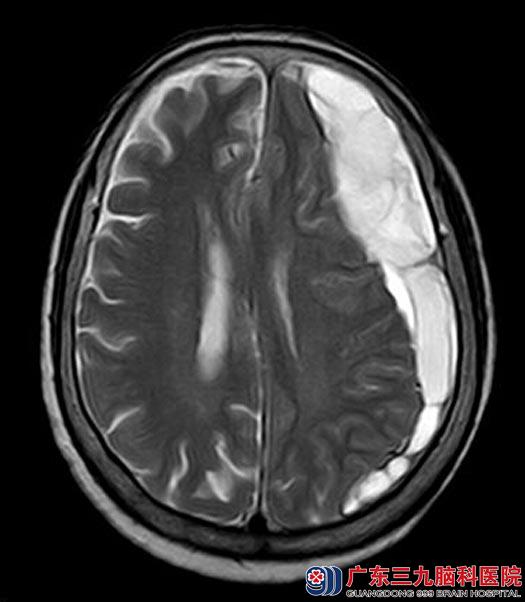

郭奶奶今年80岁高龄,十多天前出现记忆力下降,没有头痛、头晕等其它不适症状,家人未予重视;一周前郭奶奶的右侧肢体感觉乏力,家属送当地医院就诊,头颅MR检查提示:左侧额颞顶部硬膜下血肿。

手术前